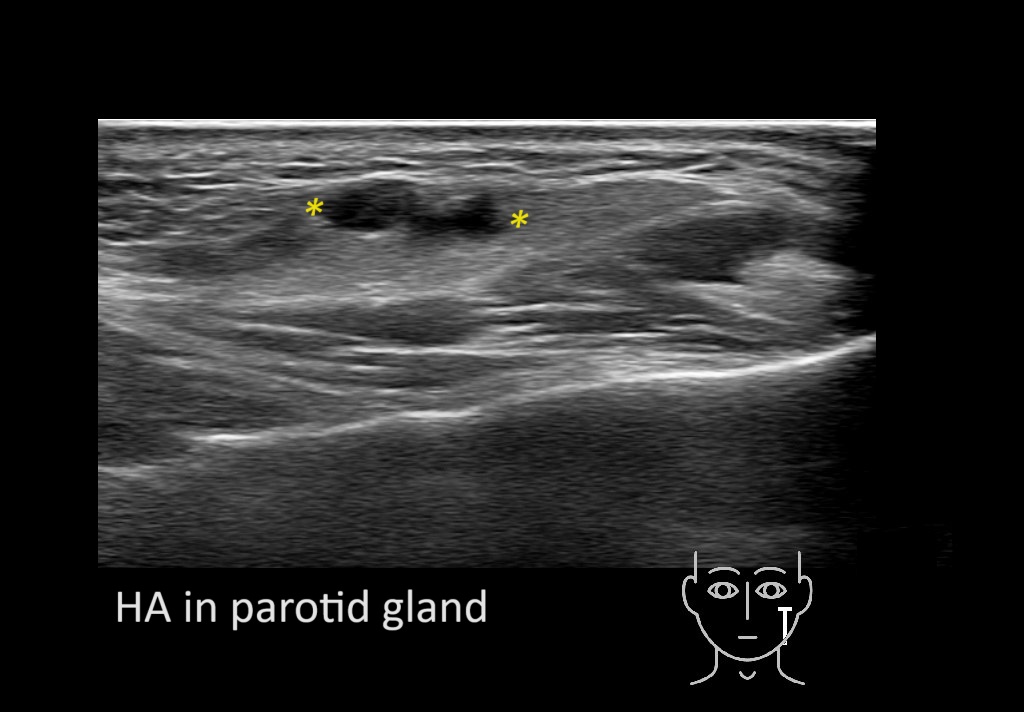

Parotid

Filler injections in the parotid gland may go unnoticed, however, inflammatory reactions and abscesses may occur. Hypervascularity can be seen with color doppler. Filler deposits are supposed to be injected into the superficial fatty layer . The space to inject into this layer may be limited. Routinely we measure a width of 2-4 millimeters with sometimes subcutaneous layers being less than one millimeter thick.